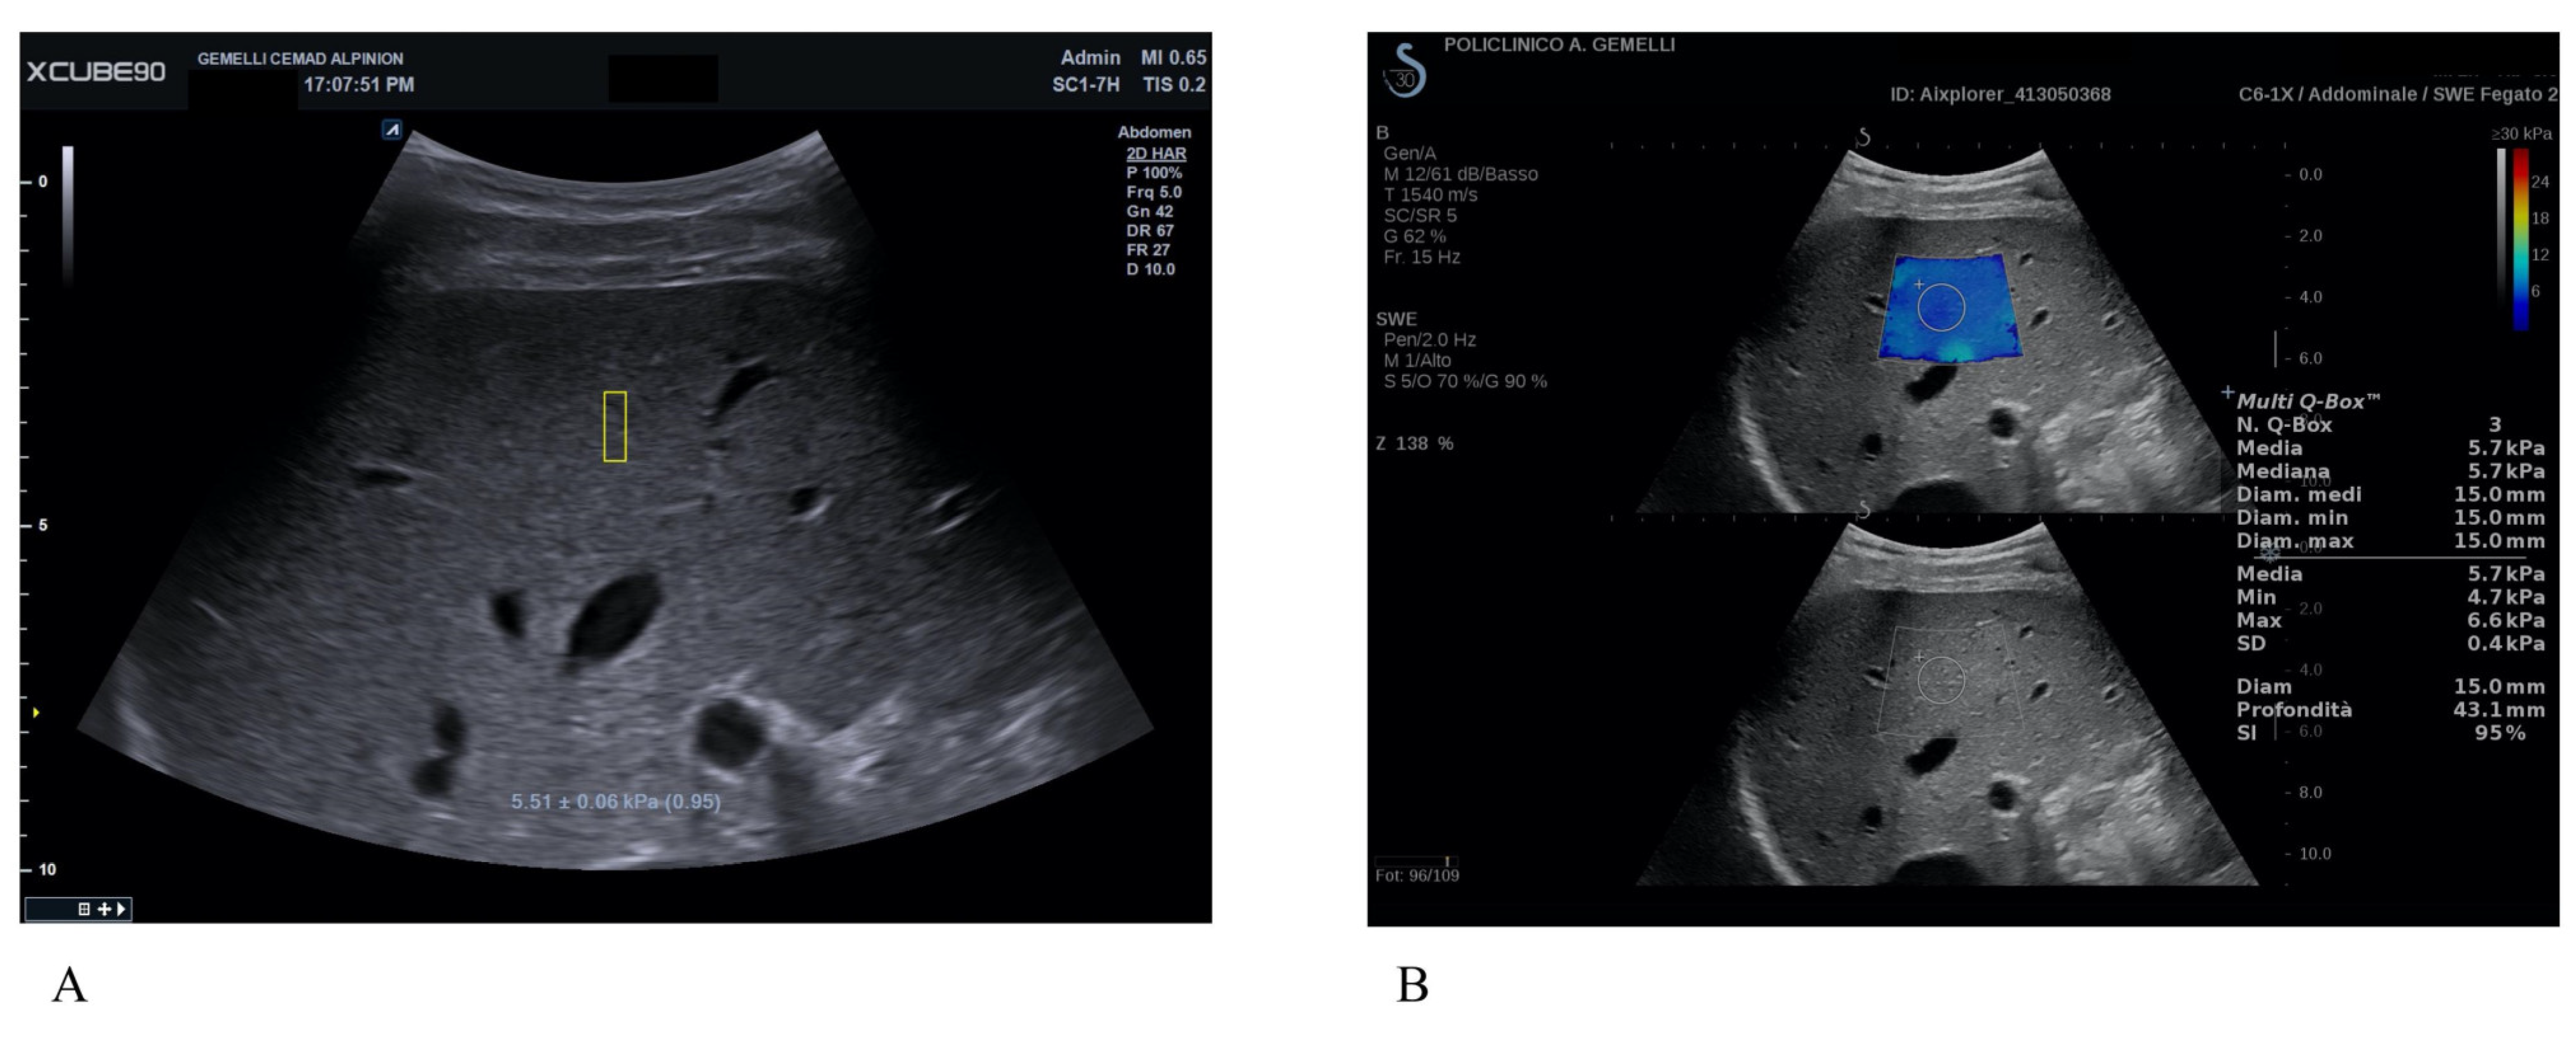

All enrolled patients underwent non-invasive measurement of LS with X-CUBE 90 (X+pSWE) (Alpinion Medical Systems Co., Ltd., Seoul, Republic of Korea) using the convex probe SC1-7H and with real-time 2D-SWE with Mach 30 Aixplorer (SSI) (Aix-en-Provence, France) using the convex probe XC6-1. The exam was performed by two expert operators with more than five years of experience with elastography techniques. The patients were assessed while supine, with the right arm maximally abducted. The probe was positioned in an intercostal region above the liver’s right lobe. During the evaluation, patients were instructed to maintain a semi breath hold, avoiding both the Valsalva maneuver and deep inspiration [9]. Ten measurements for each patient with X+pSWE were made, registering median values in kPa (M), interquartile range (IQR) and the ratio between IQR and M (IQR/M) (Figure 1A). As a further quality indicator, X+pSWE provided a number (0 to 1.00) after every LS measurement. As per vendor-specific recommendations, only acquisitions with values >0.80 were deemed reliable. For 2D-SWE with SSI, five measurements were performed using the same technique in a region of interest (ROI) of 10–15 mm in a central area of the colorimetric map showing the best signal homogeneity, registering M in kPa and stability index (SI) (Figure 1B).

Figure 1.

Shear-wave elastography (SWE) in a patient with no clinically significant liver fibrosis (F0-1). (A) X+pSWE with a median value of 5.5 kPa after 10 valid measurements; the number in the brackets (0.95) represents a reliability indicator, which provides immediate feedback about measurement quality for each single measurement specifically developed by Alpinion. (B) SSI with a median value of 5.7 kPa after 3 measurements. In 2D-SWE techniques, US images show the stiffness color map, with a homogenous blue filling that correspond to low elasticity values on the color scale.